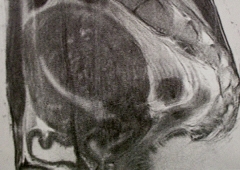

<MRI>

チョコレート嚢胞では一般的にはT1、T2ともに高信号を呈しますが、壊死部分はT2で低信号となります。

子宮腺筋症は筋層内に点状の高信号域が見られます。子宮筋腫は一般に境界明瞭な腫瘤病変なので鑑別できます。

この鑑別は99回医師国家試験でも出題されています(A39)。